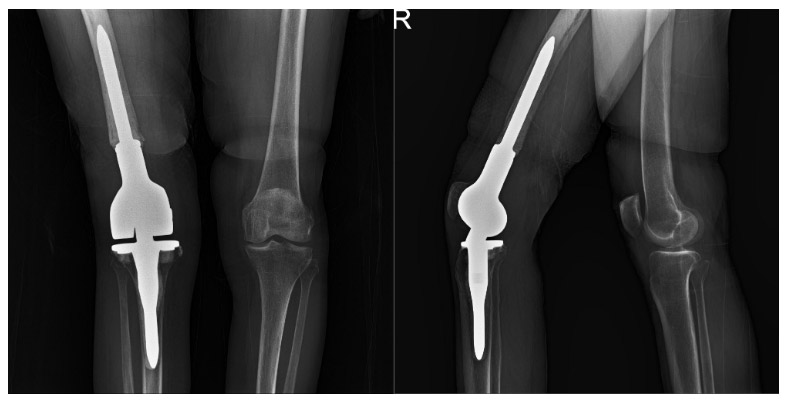

Post-surgery: The X-ray shows a distal femur tumor prosthesis implanted after resection.